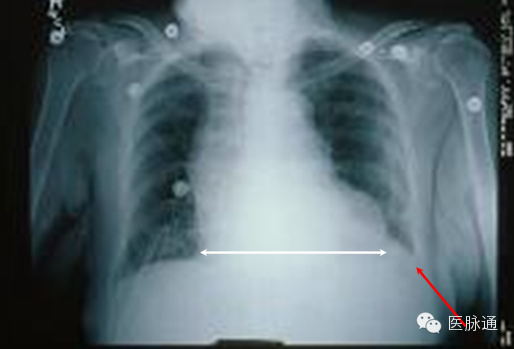

充血性心力衰竭是指心脏泵出的血不能满足组织代谢需要的临床综合征。胸片可出现多种典型的表现。心脏增大,后前位胸片显示心胸比例增加超过50%(图11白线)。小叶间隔增厚导致肺组织周边可能出现Kerley B线。胸膜液积聚可使肋膈角变钝(红色箭头)或导致大量胸腔积液。肺水肿可以引起双侧肺纹理增加,或呈蝙蝠翅状分布。肺毛细血管压增加导致上叶血管直径与下叶血管直径相当或更粗,即头侧化。

图11